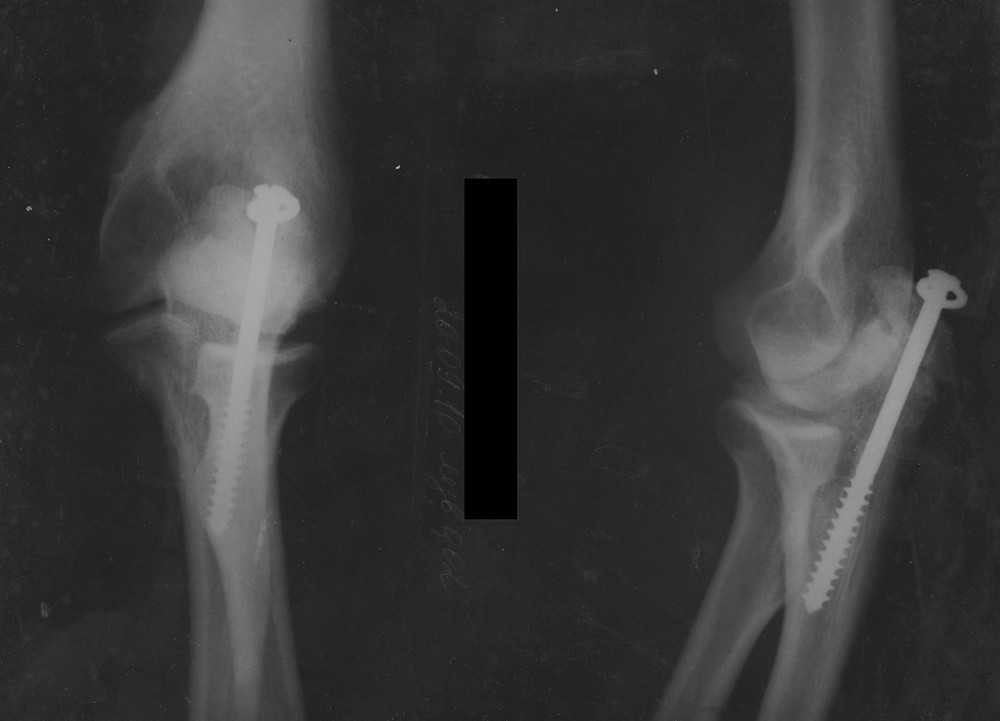

Пациент 26 лет, военнослужащий, с высокими функциональными требованиями. Курит, пьет умеренно (?..). В феврале 2009 года получает перелом локтевого отростка правой локтевой кости со смещением. При рентген-исследовании выявлен несросшийся перелом внутреннего надмыщелка правого плеча (при уточнении анамнеза вспомнил про травму в детстве). Было выполнено удаление свободно лежащего надмыщелка, синтез локтевого отростка винтом с шайбой. В послеоперационном периоде - нейропатия локтевого нерва, сейчас беспокоят незначительные парестезии в V пальце, сила кисти не страдает. При обращении (в настоящее время) беспокоит наличие металлоконструкции, "щелчки" в амплитуде сгибания от 90 до 140, (общий объем движений S 0-5-140), боль в области подкожно выступающей головки винта, субъективно - снижение силы На рентгенограмме (предоставить сегодня не смогу) - ложный сустав локтевого отростка, незначительная миграция винта. Линия ложного сустава идет косо, захватывает меньше четверти суставной поверхности. Ваши предложения? Пока выбираем между "убрать и выкинуть" и пластикой скользящим трансплантатом с фиксацией по Weber. Смущает с одной стороны - небольшой размер фрагмента, с другой стороны - итак уже надмыщелка нет, делать сустав более нестабильным не хочется. С уважением, Останин

Обещанные снимки.